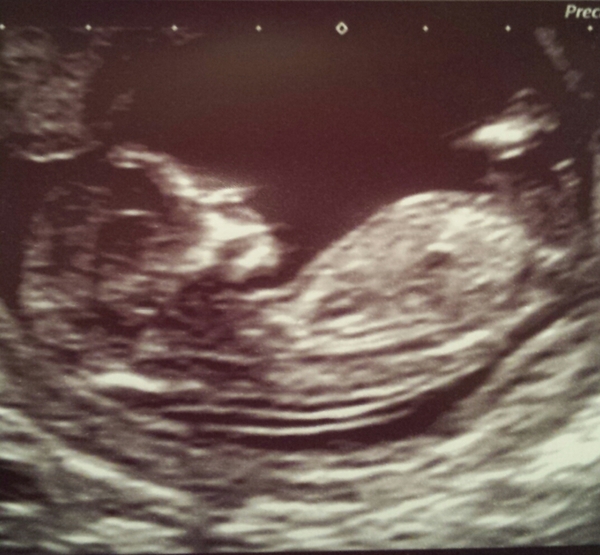

Hiya! Haven't posted in an age I'm so sorry! Had my 12 week scan today. Any gender thoughts?

MrsCK lovely scan pic, glad it went well! Looks like a boy to me :)

Mrsck I also predict a boy for you now I have finally got on desktop and seen pic!